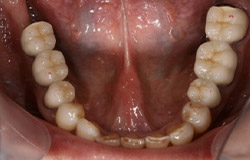

インプラントで噛み合わせの再構成を伴った症例。

治療後のメンテナンスを行わないと

周囲炎になるリスクあり。